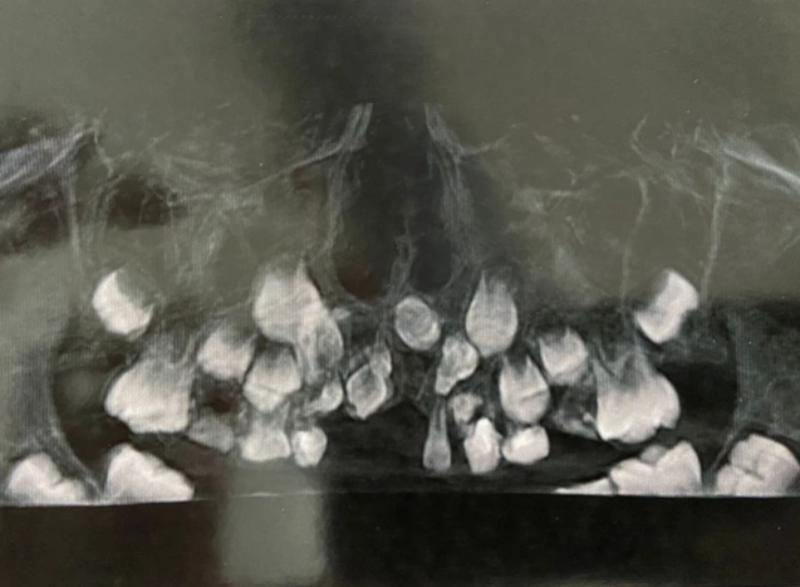

Редкая аномалия видна на снимке фото: Минздрав РО

Медики из областной детской клинической больницы помогли 8-летнему мальчику с редкой челюстной аномалией. У ребенка не росли зубы. Об этом рассказали в Министерстве здравоохранения Ростовской области.В ходе осмотра врачи обнаружили, что в верхней челюсти мальчика расположены сверхкомплектные зубы необычной формы, расположенные хаотично. Они мешали обычным зубам развиваться, а ребенку нормально жить. Это, по словам медиков, крайне редкий случай, с которым они сталкивались редко. Вызван он вероятнее всего аномалией развития.

— Технически эту операцию не назвать сложной, хотя длилась она порядка полутора часов. Но фактически процедура весьма непростая. Сверхкомплектные зубы скрыты в кости. Их видно на снимке, но манипуляция в кости несет в себе определённые риски, — сообщил челюстно-лицевой хирург ОДКБ Сергей Карнута.